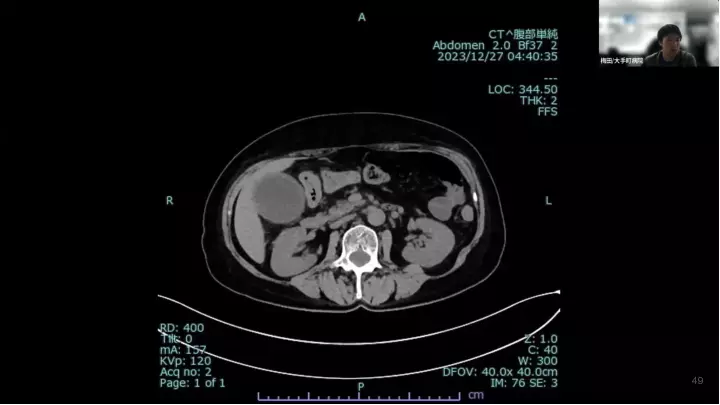

外科医目線の~急性胆嚢炎~治療編